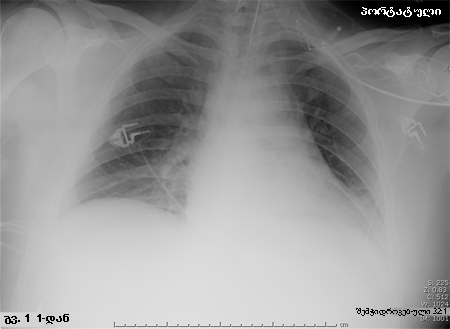

HAP-ის მქონე პაციენტის პორტატიული რენტგენოგრაფია. ყურადღება მიაქციეთ, რომ მარცხენა დიაფრაგმის თაღი არამკაფიოა მარცხენა ქვედა წილის დაჩრდილვის გამო და გულის საზღვარი ასევე არამკაფიოა მარცხენა ზედა წილის და ენისებრი სეგმენტის დაჩრდილვის გამო.